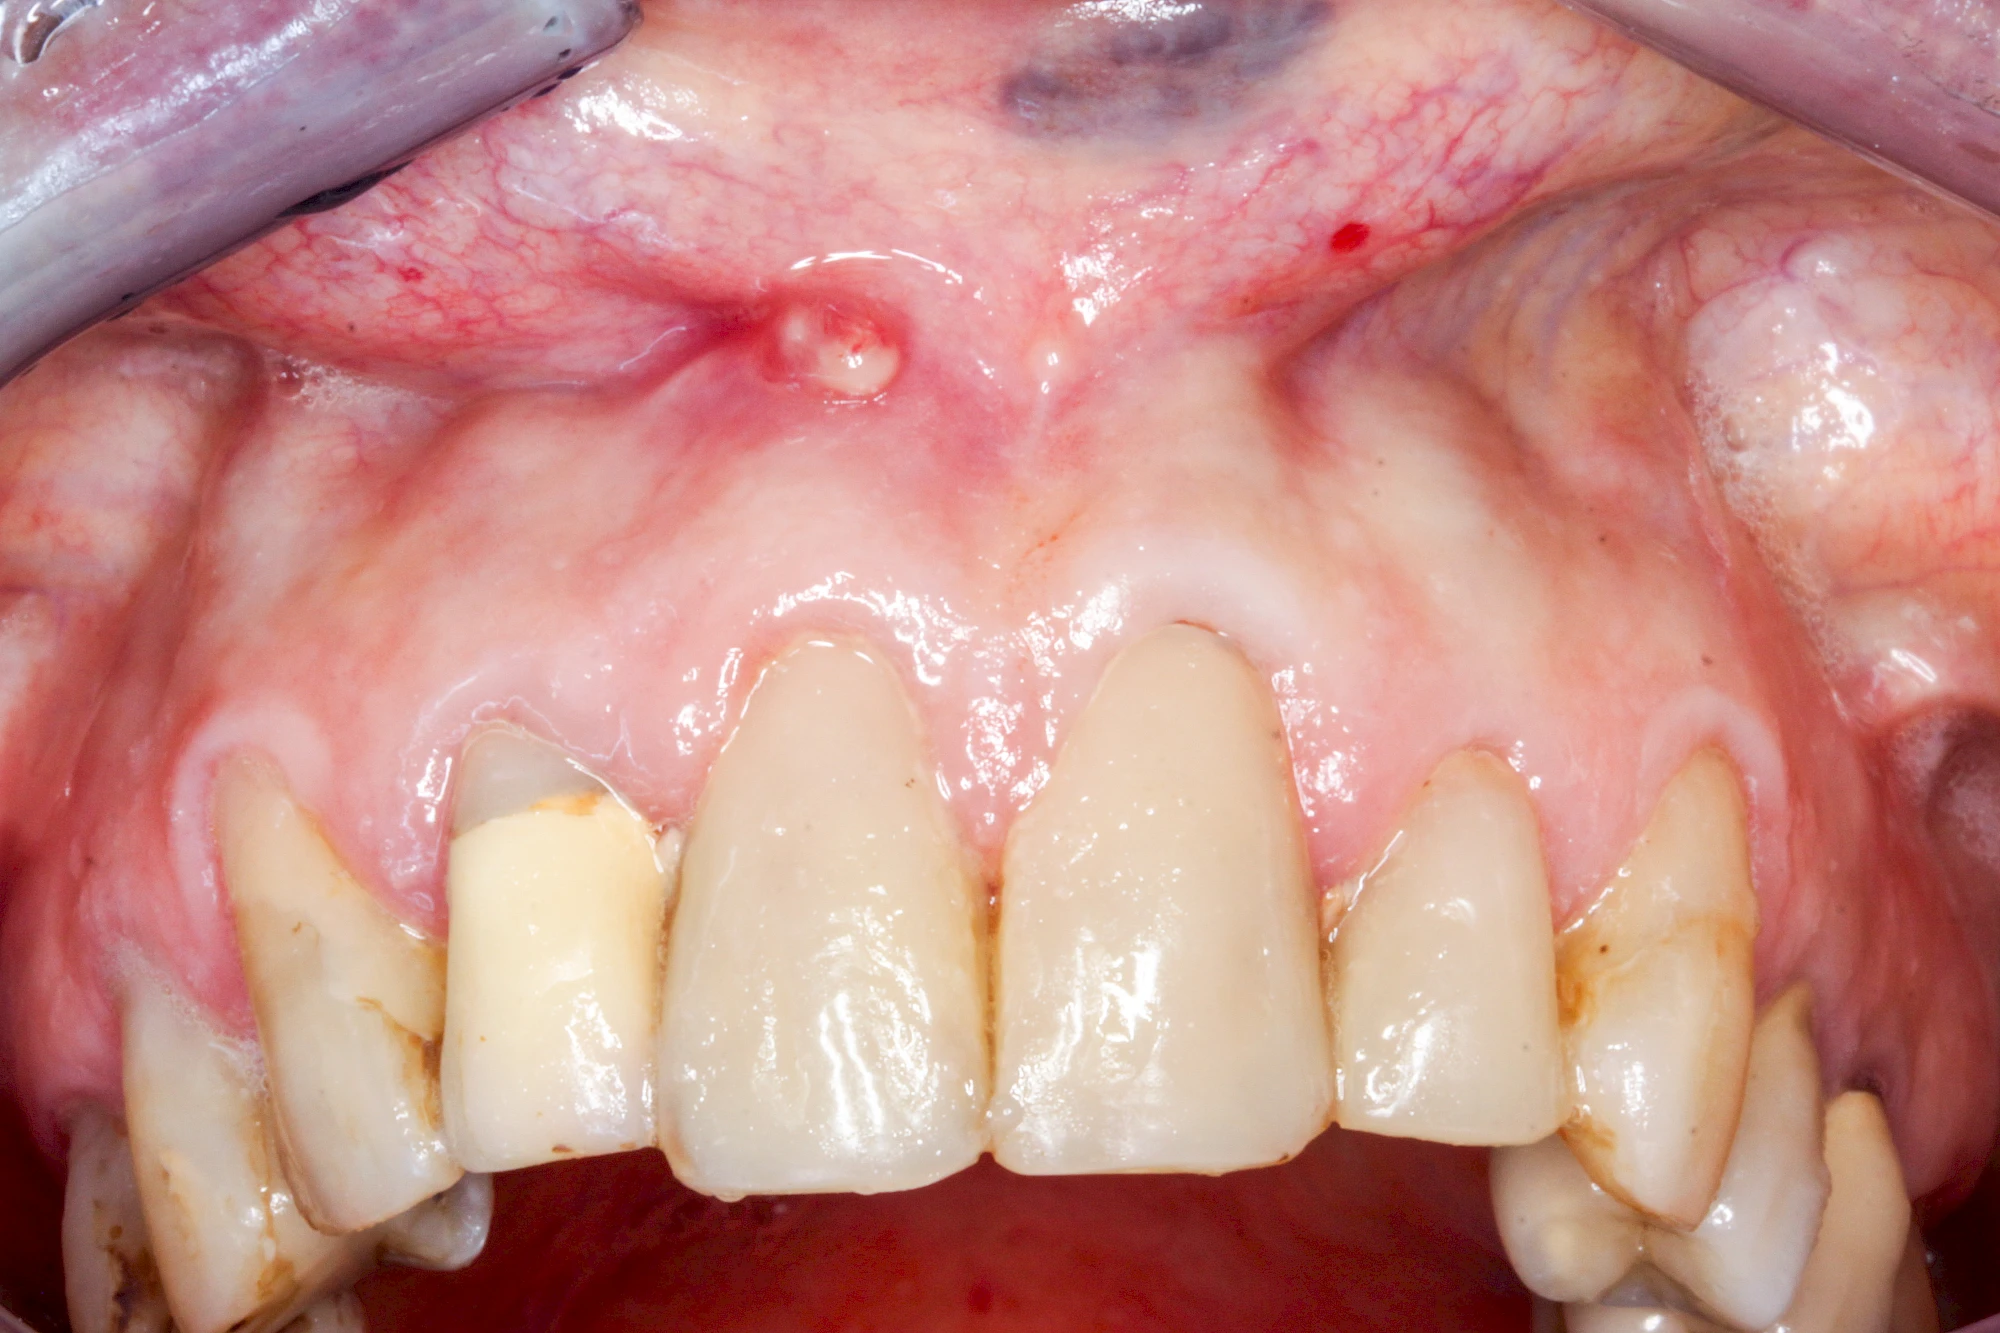

Bei einer Fistel hat sich meist eine Entzündung (manchmal auch Erreger selbst) z. B. aufgrund von Karies oder aufgrund eines Unfalls über den Zahnnerv und die Wurzelspitze (Apex) in den umliegenden Knochen ausgebreitet (apikale Parodontitis) und schnell einen Weg durch den umgebenden Knochen und die aufliegende Schleimhaut in die Mundhöhle gebahnt.

Fisteln sind in der Regel nicht schmerzhaft und fallen häufig als kleine Öffnung weiter entfernt vom Zahnfleisch nahe der Umschlagfalte auf. Aus der Fistelöffnung entleert sich spontan gelbliches Sekret (Eiter) oder es lässt sich mit dem Finger ausstreichen. Manchmal beschreiben die betroffenen Menschen immer wieder einen komischen Geschmack im Mund.

Im fortgeschrittenen Stadium kann die Schleimhaut sich weiter zurückgezogen haben und die Wurzelspitze sichtbar sein. In der Regel treten bei Fisteln keine Schwellungen auf, weil sich die Entzündung nicht im Gewebe ausbreitet.